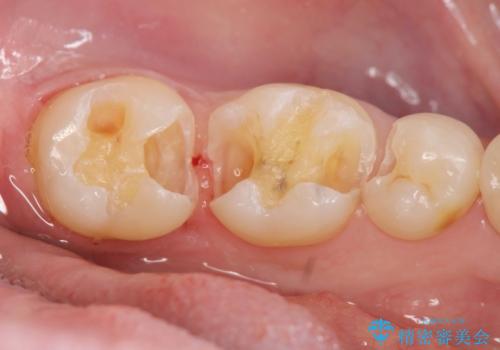

保険適応の白い詰め物レジンインレー下に再発した大きな虫歯治療

- 以前治療した歯の違和感、しみる感じの改善を求めて来院されました。

保険適応の素材、レジン素材による修復が行われていますが、X線写真より修復物の下には透過像(黒い影)が認められ、症状からも虫歯の再発が強く疑われます。